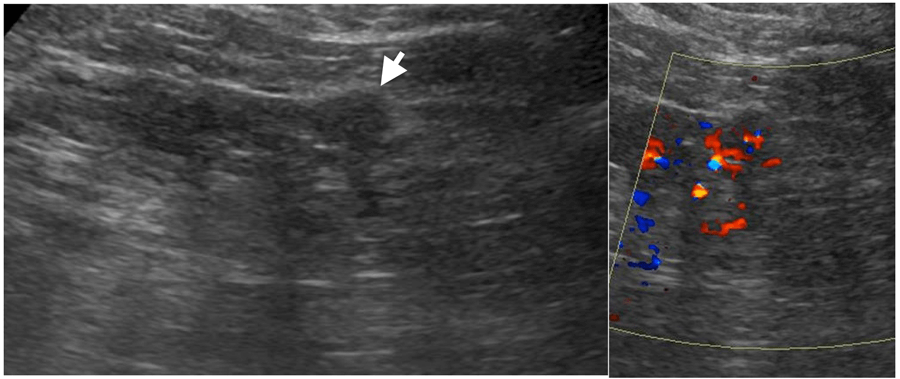

On ultrasound, solid renal masses are conspicuous only when their echogenicity is different from the adjacent renal parenchyma, there is distortion of normal renal contour or there is abnormal vascularity on colour doppler (Figure 2).

Figure 2: Small partly exophytic RCC on ultrasound (left).

Internal vascularity demonstrated on colour Doppler (right).

Figure 3: Hyperechoic 1.8cm interpolar lesion on ultrasound (left).

Unenhanced CT demonstrates macroscopic fat (-85 HU, centre).

Follow-up ultrasound at 12 months demonstrates no interval growth (right).